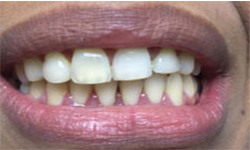

Before Treatment

After Treatment

The patient reported to the clinic with a discoloured upper lateral incisor. X Ray revealed that the tooth was root canal treated.Tooth preparation was done followed by premium zirconia crown thereby restoring the esthetics